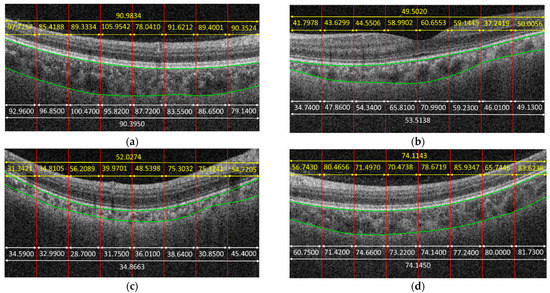

Figure 4 shows some examples to demonstrate the predicted results obtained by the proposed method. In the given examples, eight patches were cropped from a B-scan. The predicted result for each patch is shown in yellow color. The average on the predicted results of each patch cropped from the same B-scan is also in yellow. The white parts in Figure 4 are the corresponding ground truth, and green curves are the boundaries of the choroid. It is observed that the predicted results obtained by the proposed method were very close to the ground truth for some cases, e.g., Figure 4f, while the proposed method might also fail for some other cases, e.g., Figure 4c.

Figure 4.

Examples to demonstrate the predicted results obtained by the proposed method, in which yellow parts are the results obtained by the proposed method. White parts are the ground truth. Green curves are the boundaries of choroid. (a) MAE = 0.5884, (b) MAE = 4.0118, (c) MAE = 17.1611, (d) MAE = 0.0307, (e) MAE = 8.4348, (f) MAE = 0.9919.